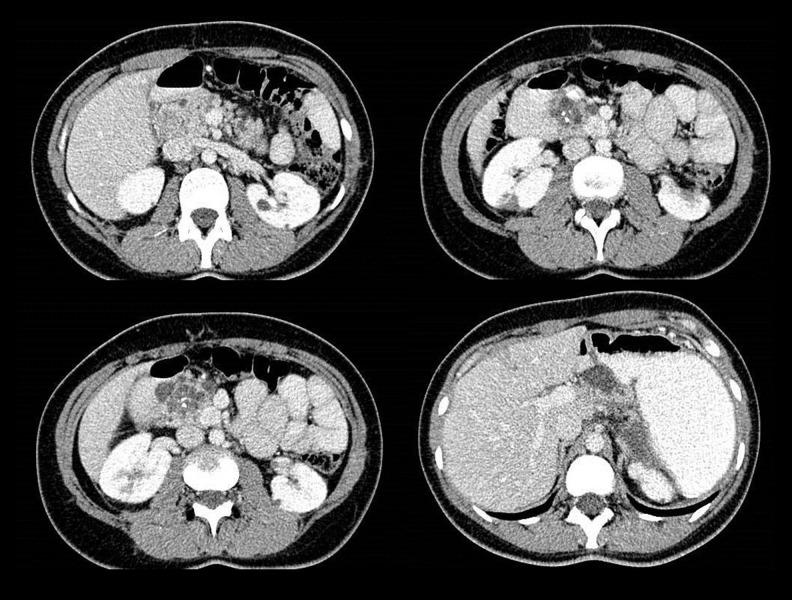

BACKGROUND Von Hippel-Lindau (VHL) disease is a rare autosomal dominant syndrome manifested by a spectrum of benign and malignant tumors.  CASE REPORT The patient presented here was a 31-year-old female with unremarkable family history who presented initially complaining of intermittent abdominal pain. Abdominal CT scan revealed an inhomogeneous solid mass (13×9×7 cm) originating from the tail of the pancreas with splenic and gastric invasion as well as several pancreatic cysts. A nucleotide scan showed left adrenal involvement. The patient underwent tumor resection, splenectomy, partial gastrectomy, and left adrenalectomy. Histopathologic examination reported well-differentiated neuroendocrine carcinoma with low malignant potential of the tumor with splenic and adrenal involvement. Pancreatic cysts had benign component.  Three years later, follow-up abdominal CT showed heterogeneously-enhanced solid nodules in both kidneys found to be renal cell carcinoma (RCC) on biopsy. At the same time, brain MRI showed cerebellar hemangioblastomas. Partial nephrectomy was done. Molecular genetic testing for demonstrated NM_000551.3:c.481C > T (p.R161* CGA>TGA), which has been reported previously in VHL disease. The next year, she developed peritonitis, which found to be the result of a perforated gastric ulcer. Histopathologic examination of the ulcer revealed neuroendocrine carcinoma. Then, the next year, a brain MRI revealed 4 solid and enhanced nodules in the cerebellum, suggesting multiple hemangioblastomas. Octreotide (Sandostatin® LAR) and everolimus (Afinitor®) were started for the patient. At the last visit, the patient was asymptomatic with acceptable condition.    CONCLUSIONS Here, we present a young patient with pancreatic neuroendocrine tumor as the first presentation of VHL without a remarkable family history for VHL disease. The patient developed RCC, renal cysts, cardiomegaly, and brain hemangioblastomas during the 8-year follow-up. Regular follow-up with imaging (ultrasound, CT, MRI) are necessary to follow the previous lesions and detect any newly-developed VHL-associate tumors.

病例报告 本文介绍的患者是一名31岁女性,家族史无异常,最初因间歇性腹痛就诊。腹部CT扫描显示一个不均匀实性肿块(13×9×7 cm),起源于胰尾,侵犯脾脏和胃,还有几个胰腺囊肿。核苷酸扫描显示左肾上腺受累。患者接受了肿瘤切除术、脾切除术、部分胃切除术和左肾上腺切除术。组织病理学检查报告为高分化神经内分泌癌,肿瘤恶性潜能低,累及脾脏和肾上腺。胰腺囊肿有良性成分。

三年后,腹部CT随访显示双肾有不均匀强化的实性结节,活检发现为肾细胞癌(RCC)。同时,脑部MRI显示小脑成血管细胞瘤。进行了部分肾切除术。分子基因检测显示为NM_000551.3:c.481C>T(p.R161* CGA>TGA),此前在VHL病中已有报道。次年,她发生了腹膜炎,发现是胃溃疡穿孔所致。溃疡的组织病理学检查显示为神经内分泌癌。然后,又过了一年,脑部MRI显示小脑有4个实性强化结节,提示多发成血管细胞瘤。开始为患者使用奥曲肽(善龙®长效注射剂)和依维莫司(飞尼妥®)。在最后一次就诊时,患者无症状,情况尚可。